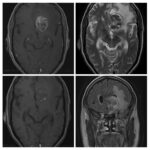

Neurosurgery and neuroradiology always go hand in hand. This little weekly activity is going to enhance the scan reading skills of our audience in an interactive way. Waiting for the answer for a week will keep the curiosity alive and will keep our target audience hooked to the website. It will prove to be a seamless share of knowledge and reading skills.

Dr. Saqib Kamran Bakhshi started the PANS Weekly Image Challenge in 2022, and his creativity and efforts made it a popular activity; engaging trainees and consultants in Pakistan and abroad.